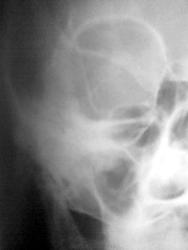

Ну разве только эта тенюшка?

Мерещатся два: одно в проекции малого крыла, второе чуть выше и медиальнее.

Если б я эти резиновые пули когда-нибудь видела, Хоть бы размер знать... Попытка №2

На 1 см выше и влево))))

В проекции основной пазухи?